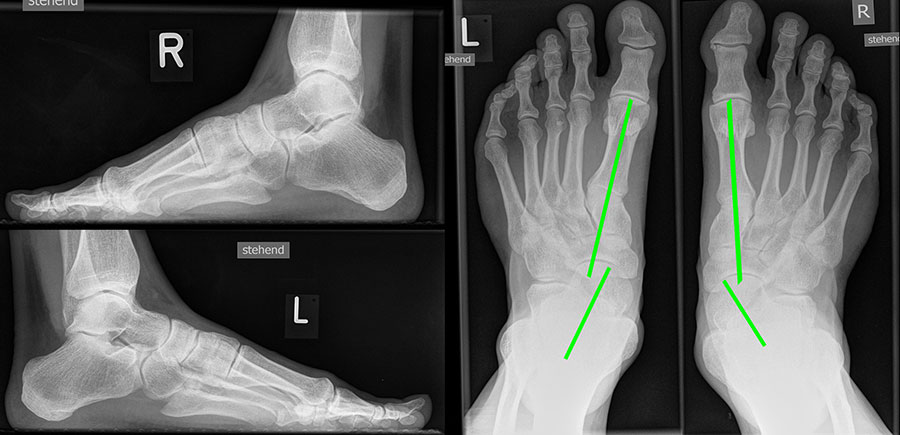

Vermehrter Rückfußvalgus links bei chronischer Instabilität des Deltabandes. Die wichtigste Differenzialdiagnose ist die Insuffizienz der Tibialis posterior Sehne.

Abbildung 2

Bei Insuffizienz der tibionavicularen Bandanteile oder des Spring-Ligaments zeigen die konventionellen Aufnahmen eine Konstellation wie bei einer Tibialis posterior Insuffizienz mit Vorfußabduktion, eingesunkenem Längsgewölbe und vermehrtem Rückfußvalgus (Abbildung 3).